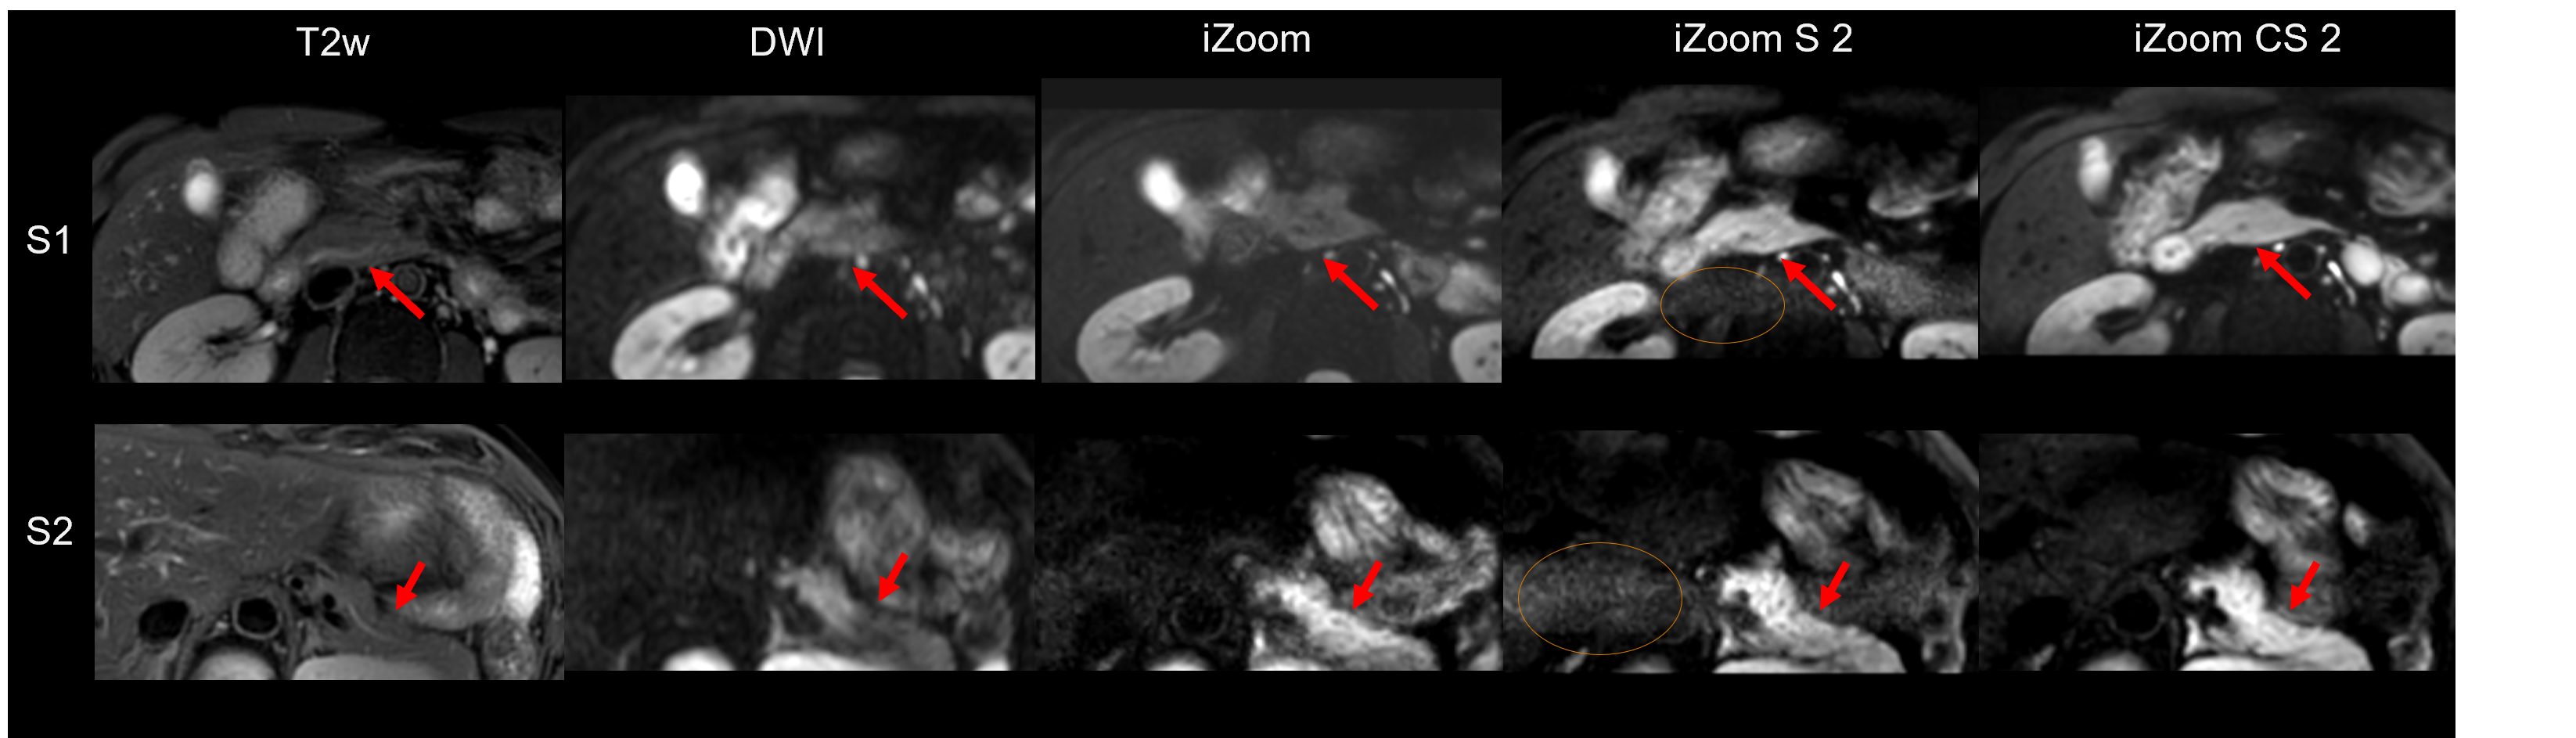

Pancreas imaging of T2w, conventional DWI, and reduced FOV imaging through iZoom with SENSE or Compressed Sense (CS) were shown for 2 axial planes (S1, S2) in Figure 1. Compared to conventional DWI, reduced FOV imaging provided better tissue contrast, and iZoom combined with CS (iZoom-CS2) clearly improved the image quality with regard to denoising (regions with red arrows). iZoom with parallel imaging (iZoom-S2) had banding noise (as circled in Figure 1) and was not practically useful. Figure 2 shows the high resolution (1.5 x 1.5 mm2) pancreas imaging compared with iZoom-CS of baseline resolution (2 x 2 mm2). iZoom with CS = 2 high resolution imaging (iZoom-CS2-HR) provided an optimal high resolution pancreas DWI image, preserving fine structures (see magnified regions). iZoom with CS 3 images suffered from banding noise artifact.

Figure 1. Pancreas imaging of T2w, conventional DWI, and reduced FOV imaging through iZoom with Sense or Compressed Sense (CS) were shown for 2 axial planes (S1, S2). iZoom-CS2 clearly improved the image quality through denoising (regions with red arrows). iZoom-S2 has the noise breakthrough as circled.